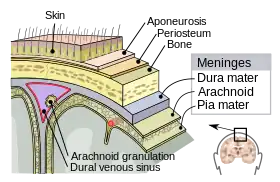

The meninges in multiple sclerosis

The meninges are three layers that protect the brain and the spinal cord. They are called (from the outside to the inside) the dura mater, the arachnoid mater and the pia mater. The cerebrospinal fluid flows between the second and the third one. A remarkable finding in MS is that some Follicle-like aggregates appear in the meninges (composed by B-cells mostly infected with EBV[4]). These aggregates grow during the disease process and is mostly found in secondary progressive patients.

Inflammation in the meninges has been found to be associated to gray mater (cortical) demyelination. Besides subpial demyelination suggest either a problem in the CSF or in the pia mater that should protect the cortex[87]

Whatever the underlying condition for MS is, some damage is triggered by a CSF unknown soluble factor, which is produced in meningeal areas and diffuses into the cortical parenchyma. It destroys myelin either directly or indirectly through microglia activation.[6]

The infiltration into meninges, which has been referred to as Tertiary Lymphoid Tissues (TLTs), prepares the infiltration into the CNS parenchyma causing demyelination in subpial and cortical areas. Animal models suggest that infiltrating Th17 cells remodel the meningeal stromal (non-immune) cells and initiate the formation of TLTs during EAE. The remodeled stromal cells retain and promote the production of Th17 and the accumulation of B cells. The collaboration between LTB on Th17 cells and LTBR (Lymphotoxin beta receptor) on meningeal radio-resistant cells is very crucial for the induction and progression of MS.[88]